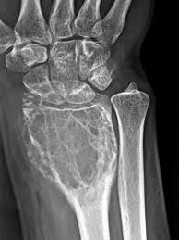

Age of onset of giant cell tumor of bone